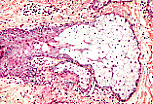

皮脂腺与毛囊的结合关系。

切片平面未必能同时显示毛囊与表皮的连接部,以及皮脂腺与分泌皮脂的毛囊的连接部。因此在本图像中,部分毛囊和部分腺细胞群看似孤立分布于结缔组织中。 |